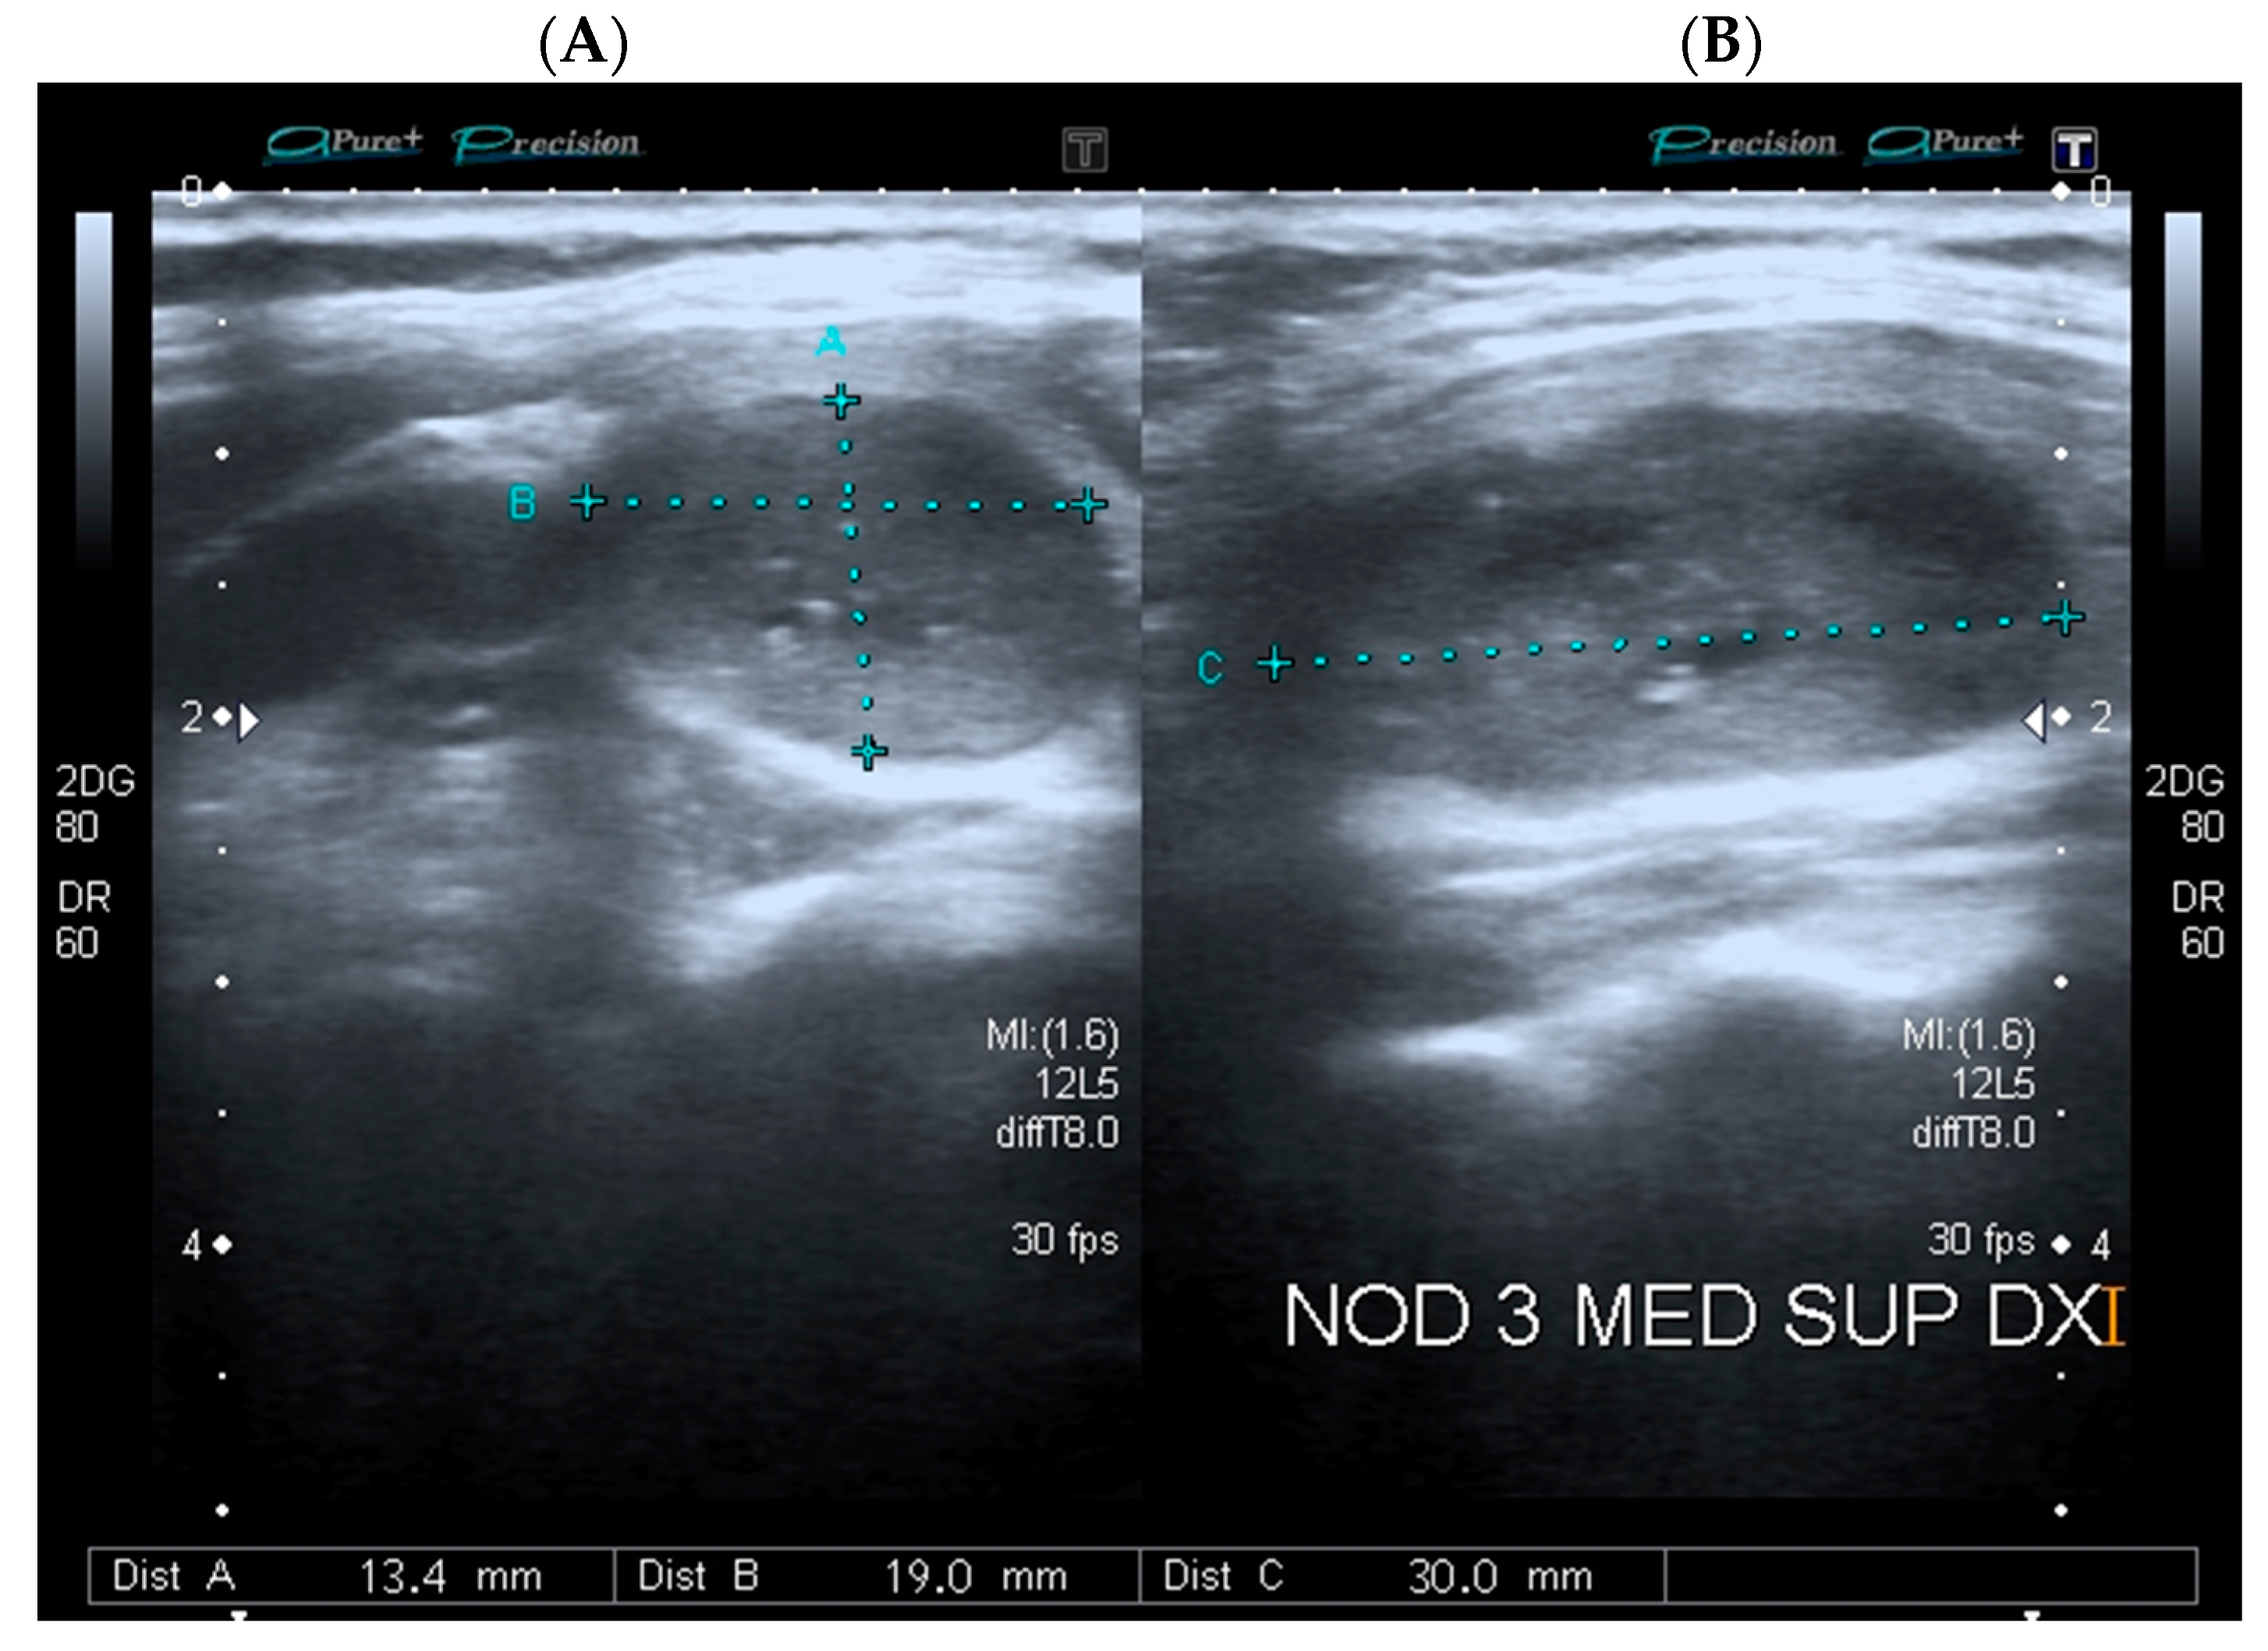

Real-time US assessment was performed on longitudinal and transverse planes with the use of a high-resolution ultrasound system (10 MHz, Aplio XG, Model SSA 790A, Toshiba Corp., Tokyo, Japan) by two expert endocrinologists, trained in cervical sonography, under routine clinical practice conditions. Standardized US description of thyroid lesions included position, composition, echogenicity, presence of calcifications, margins, vascularity, size, and shape. Position was defined as the location of a nodule within the thyroid gland in relation to isthmus, left lobe or right lobe. The composition was defined based on the ratio of the cystic component to the nodule volume as solid (liquid component ≤10%), mixed (liquid component >10% and ≤90%), cystic (liquid component >90%), and spongiform (multiple heterogeneous microcystic areas separated by thin septations occupying ≥50% of the nodule volume). Echogenicity was defined as the predominant brightness of the solid component of a nodule in comparison with thyroid parenchyma and/or adjacent infrahyoid muscles, using the following terms: isoechoic, hyperechoic, hypoechoic (relative to thyroid parenchyma), marked hypoechoic (relative to adjacent infrahyoid muscles), and anechoic (in case of cystic lesions). When present, calcifications were classified as micro- (<1 mm intranodular hyperechoic punctate foci), macro- (>1 mm hyperechoic foci), and peripheral rim calcifications. In order to improve visualization and assessment of microcalcifications, which are US features suspicious for malignancy, additional Micropure™ image processing (Aplio XG, Toshiba Corp., Tokyo, Japan) was used [31]. Margins were described as per definition (presence or absence of a clear demarcation between the nodule and the surrounding thyroid parenchyma) and regularity (absence or presence of edges and/or lobules) as well-defined, ill-defined, regular, or irregular. Nodule vascularity, with reference to the amount and distribution (peripheral or central) of blood flow on Power Doppler US analysis, was described as absent, perinodular, intramodular, and peri-intranodular. To estimate nodule size, three diameters were measured: AP, LL, and L diameter. The AP and LL diameters were measured on the transverse scan as the largest nodule dimensions from front to back and side to side, respectively, whereas the L diameter was measured on the longitudinal scan as the largest dimension from side to side (Figure 1). The maximum diameter of the nodule was defined as the largest diameter on any imaging plane. Nodule volume and surface were calculated using the ellipsoid formulas. Based on comparisons among AP, L, and L diameters, nodule shape was defined as round (when the AP diameter was equal to LL and L diameters), ovoid with parallel orientation (when the AP diameter was shorter than LL and L diameters) and taller-than-wide with nonparallel orientation (when the AP diameter of a nodule was longer than its LL or L diameter). Cervical lymph nodes were classified as normal or, in case of one or more suggestive US features (e.g., round shape, absence of an echogenic hilus, hypo- or hyper-echogenicity, presence of calcifications, or structural and vascular changes) as suspicious [32]. US data were collected and stored for further analysis. Sets of US features were reviewed from digital medical records to classify the malignancy risk of thyroid nodules, according to the internationally endorsed ATA [25], AACE/ACE/AME [1,26] and ACR-TIRADS [27] US risk stratification systems. By using the approach reported in a previous study with similar retrospective design [33], a yes or no answer to each of the US features derived from the ATA, AACE/ACE/AME, and ACR-TIRADS guidelines were input, for the index nodule, into a prespecified Microsoft Excel worksheet (Microsoft Office 2016, Redmond, WA, USA) and then fitted into the correspondent category for the relevant system. However, in our work, the investigator responsible for data input was not blind to cytological and histological outcomes [33].

Figure 1.

Representative image of a thyroid nodule measured on (A) the transverse plane; (B) the longitudinal plane. Blue electronic calipers are showing automated measurements of nodule diameters.

Logistic regression analyses showed a strong association between irregular margins (OR 8.143 (95%CI 4.547–14.582); p < 0.001) and risk of thyroid cancer. Malignancy risk appeared higher in nodules smaller than 10 mm (OR 5.413 (95%CI 1.442–20.326); p = 0.012), notwithstanding wide uncertainty intervals around the estimate due to limited data. Indeed, only a few benign nodules in this study had a diameter smaller than 10 mm, as current Italian guidelines, based on AACE/ACE/AME, do not reccomend FNA or surgery in these cases, in absence of an high-risk US appearance or patient’s specific factors [1,26] (Table 2). Moreover, solid composition (OR 3.829 (95%CI 2.071–7.079); p < 0.001), microcalcifications (OR 2.843 (95%CI 1.293–6.250); p = 0.009), and marked hypoechogenicity (OR 2.78 (95%CI 1.780–4.342); p < 0.001) were strong predictors of thyroid cancer, as well as patient’s age ≤ 20 years (OR 3.966 (95%CI 1.350–11.651); p = 0.012) and between 21–30 years (OR 3.737 (95%CI 3.737); p < 0.001). Remarkably, a measured difference between L and AP diameters >5 mm, a proxy for an oval-shaped and parallel-oriented nodule (as the one shown in Figure 1), emerged as a robust protective factor against thyroid cancer (OR 0.288 (95%CI 0.817–0.443); p < 0.001). The other clinical and US categorical factors associated with benign nodular disease were patient’s age between 51–60 years (OR 0.581 (95%CI 0.345–0.978); p = 0.041) and a maximum diameter larger than 40 mm (OR 0.368 (0.819–0.718); p = 0.003). No association was observed with male gender, intranodular vascularity, or a maximum diameter of 10–40 mm. Figure 2 shows the association between demographics, US and cytological features, and thyroid cancer.